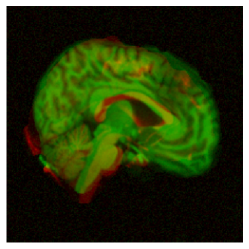

|

pre-aligned |

![]() |

|---|---|---|---|

large deformation |

| before registration | SVF | (ours) |

To motivate our work, consider the example in Fig. 1, in which we performed a 3D registration of two MRI brain scans from the OASIS [7] dataset using the popular Stationary Velocity Field (SVF) approach [8, 9, 10] and our proposed method (denoted ). In the first example, the sought deformation is comparably small before the registration process, and both approaches perform equally well. In the second example, the deformation includes a larger rotational component. When looking at the deformed images only, the SVF approach appears to generate an alignment that is clearly worse, but not catastrophically so. This is deceptive: inspecting the generated deformation fields (Fig. 2), it becomes clear that the SVF approach generates a deformation that – while it maps corresponding intensity values reasonably well between the images – is far from the ground truth.

This behavior is clearly visible in Fig. 1 and Fig. 2 shown in the introduction, in which the resultant images as well as an exemplary slice of the deformation field are depicted under small and large deformations. It illustrates how the matrix group approach is able to capture even large rotational deformations, whereas the use of an SVF tends to align the intensity values by local deformations instead of a global rotation, resulting in the large RMSE observed in Fig. 12.